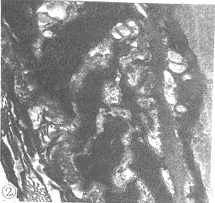

2.2超微结构A组肺小动脉内膜光滑,内皮细胞单层扁平排列,中膜平滑肌环状排列,外膜少许胶原纤维(图1)。B1组肺小动脉内膜粗糙,内皮细胞呈立方形,胞内见水肿空泡形成,内皮下水肿明显,内弹力膜增厚并且弯曲,中膜细胞竖立呈垂直排列,其间见胶原纤维;外膜纤维母细胞增生,内质网扩张,其周胶原纤维密集排列(图2)。B2组内、外膜改变同B1组,中膜平滑肌变成环状排列,面积缩小(图3)。C1、C2病变相似,均出现中膜、外膜广泛纤维化以及中膜平滑肌竖立,不过C1组纤维化尤重(图4,图5)。

图2B1组电镜见内皮细胞竖立,胞内水肿,出现空泡。平滑肌细胞排列紊乱(×8000)